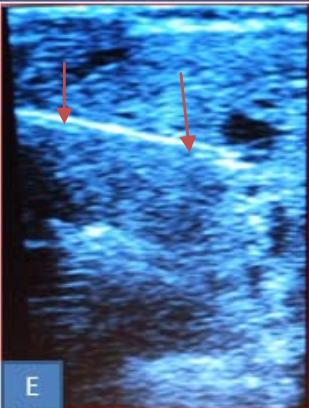

Iconography B: Patient with a 108 ml right isthmo-lobar thyroid hematocele during the first drinking session. A. Materials used before sclerotherapy, B. Image showing a right anterior and lower cervical swelling, Ultra sonographic image: showing a hypoechoic mass dotted around the partitions of 108 ml, D. image showing after ultrasound-guided puncture showing hematic content in the syringe, E. Ultra sonographic image in B mode, showing linear hyper echogenicity of the needle.